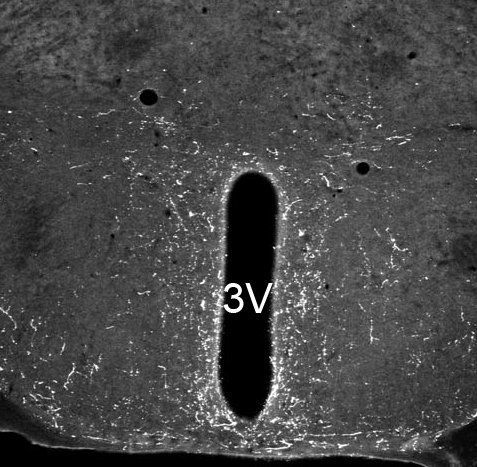

IHC-P analysis of mouse hypothalamus tissue using GTX79392 Neuropeptide S antibody.